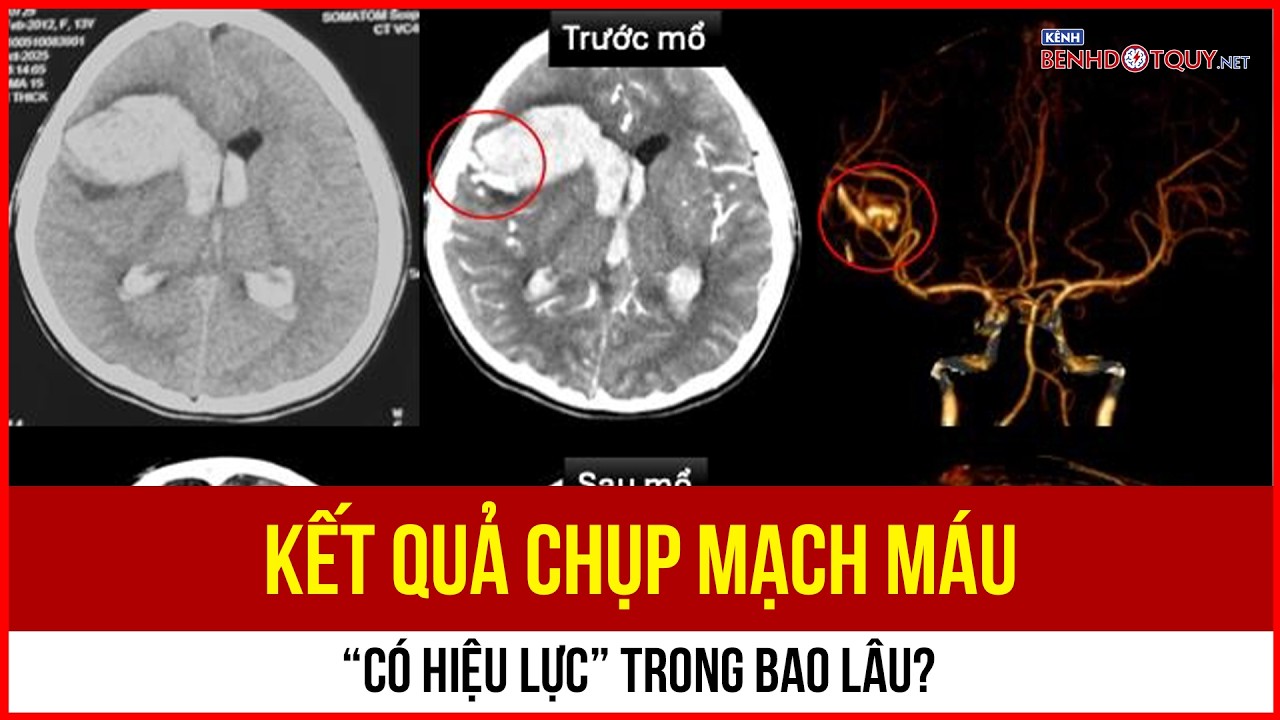

Kết quả chụp mạch máu “có hiệu lực” trong bao lâu?

Kết quả chụp mạch máu là căn cứ quan trọng giúp bác sĩ chẩn đoán và theo dõi bệnh lý tim mạch, đột quỵ. Tuy nhiên, nhiều người vẫn băn khoăn liệu những hình ảnh này có thể sử dụng trong bao lâu trước khi cần chụp lại. Thực tế, “giá trị” của kết quả không phải lúc nào cũng cố định, mà phụ thuộc vào diễn tiến bệnh và tình trạng sức khỏe của từng người.